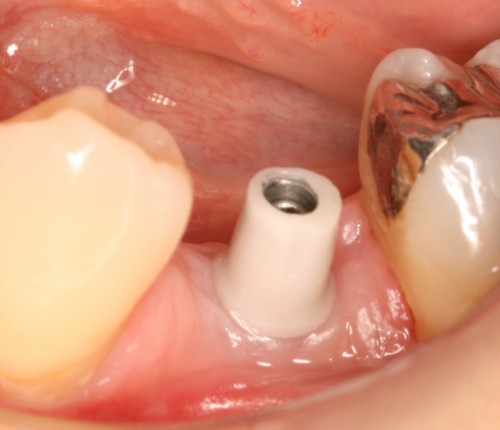

術前

左下5部 乳歯晩期残存

抜歯後

インプラント埋入直前

インプラント埋入直後

埋入後約3ヶ月

オペ時のISQ値

土台装着

被せ物装着

被せ物装着後